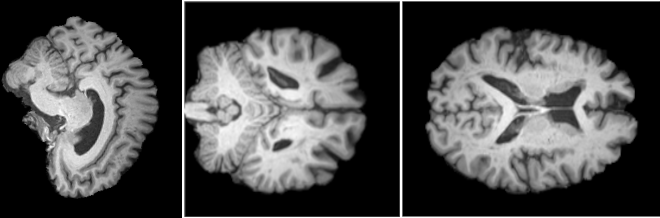

This chapter presents the main components of the proposed Fractal Space-Curve Analysis (FSCA). The stages of the method are illustrated by the flowchart in Fig. 1. The data of any of several possible types—(a–c) in Fig. 1—are first cut into two-dimensional slices (d), then each of the slices is turned into a time series with the help of the Hilbert space-filling curve (e), and, finally, detrended fluctuation analysis is applied to each time series to extract the Hurst exponents. The generated interpretable output is of a type depending on the dimensionality of the input data (g–i).

4.1 Structural MRI data analysis: Alzheimer’s disease

Alzheimer’s disease (hereafter AD) is a neurodegenerative condition impacting over 50 million individuals globally [44], recognized as the predominant cause of dementia. While diagnosing severe stages of AD is straightforward, identifying its early stages poses a significant challenge [45]. Among the conventional diagnostic tools employed, magnetic resonance imaging (MRI) stands out, as it provides detailed anatomical images of the brain. In this paper, we use FSCA to analyze MRI datasets obtained from patients in the advanced and early stages of AD. We implement standard preprocessing procedures for every MRI scan, resulting in a three-dimensional data volume of voxels. Each voxel encapsulates of brain matter volume. We apply FSCA to each slice independently along the , , and axes (e.g. see Supplementary Fig. 1) and conduct the final fractal analysis. This procedure generates a list of Hurst exponents that vary along the sliced axis (hereafter called the Hurst profile), offering valuable and interpretable insights into the local fractal properties of the brain.